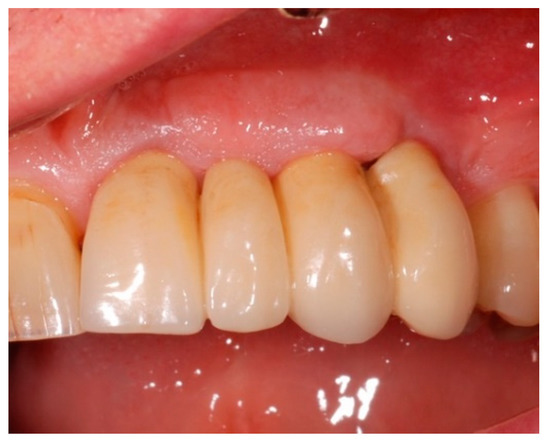

2.1. Demographics

2.2. Clinical Outcomes

4. Materials and Methods

4.1. Study Design

4.4. Study Protocol and Treatment

4.5. Test Substances and Administration